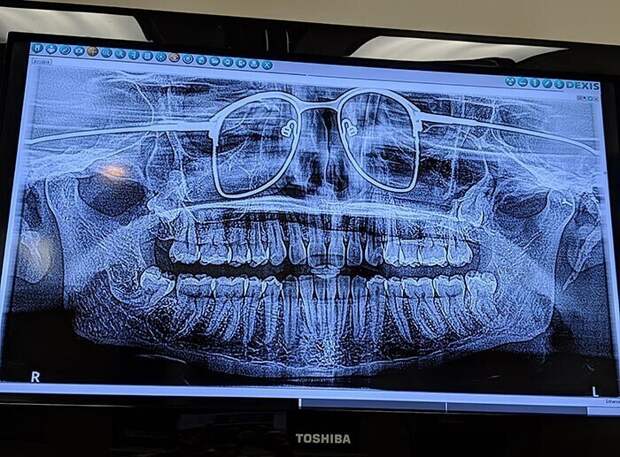

«Вчера у дантиста делал панорамный снимок зубов. Забыл снять очки»